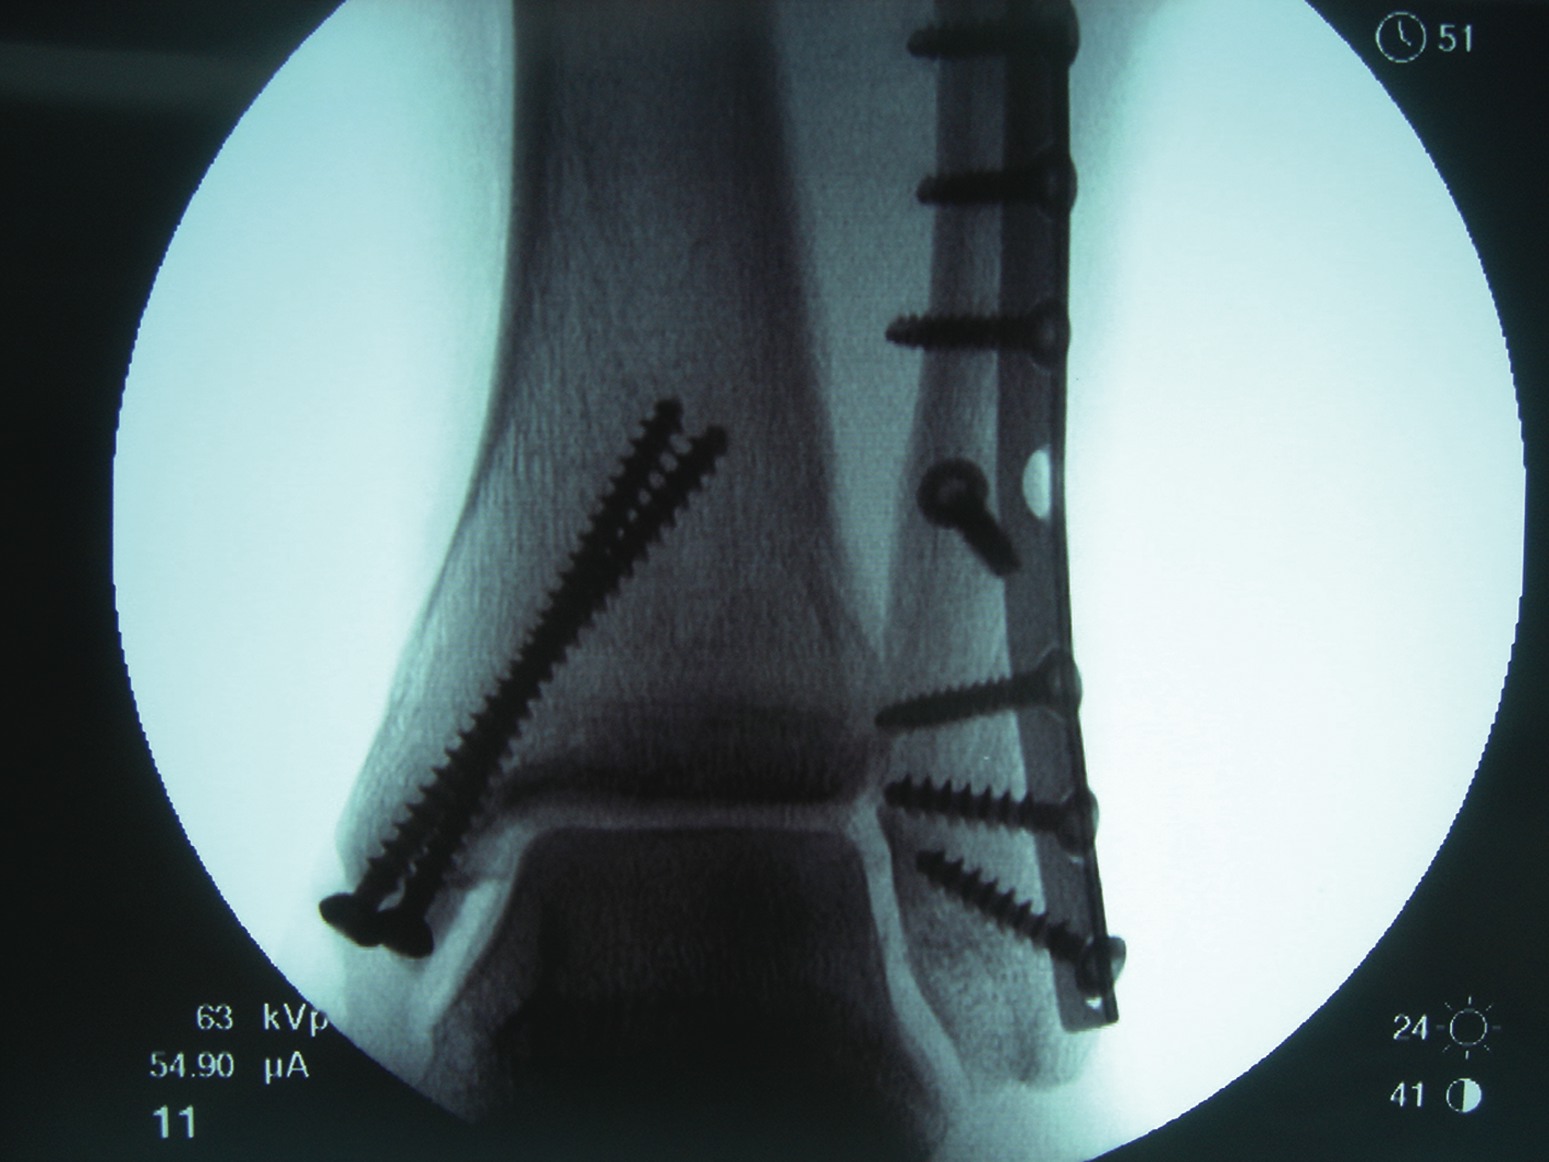

All athletes, regardless of the level of performance, will need the appropriate physical therapy modalities and rehabilitative techniques to complete functional recovery from an ankle fracture. Athletes who are at the competitive amateur level or professional level will need to return to their performance level sooner than the weekend warrior. Athletes whose career is based on their performance and return to competition will need complete rehabilitation. These individuals have no financial constraints as compared to some amateur athletes and recreational athletes. There are three phases of rehabilitation: the acute phase, the recovery phase and the functional phase. Phase one is the reduction of pain, inflammation and edema while retarding muscle atrophy of the lower extremity complex. Improving range of motion is also a major component in this acute phase. Phase two involves improving range of motion, improving lower extremity strength, increasing neuromuscular control and regaining normal arthrokinematics (defined as function of the joint) in single planes and triplanar motion of the ankle. Phase three involves increasing power of the lower extremity complex, increasing neuromuscular control in multiple planes of motion and utilizing sport-specific training for a full return to sport.30,31 A consideration with treating athletes is that if the athlete is inactive after his or her injury, the athlete loses training adaptation. This means the athlete will “detrain” as the individual’s physiological function reverts to the normal untrained state.32 It is most essential that the athlete remain active in some form of alternative exercise or maintenance program during the rehabilitative period in order to maintain his or her mental and physical strength. Alternative activities include water running and weight training of the upper extremity and the noninvolved lower extremity. Any form of maintaining aerobic capacity, neuromuscular coordination and muscle strength will help reduce injury.30 When it comes to ankle fractures in competitive athletes who require full function of their joints and motion, these individuals will need complete reduction with no malalignment. In previous studies, authors have shown that 1 to 2 mm of displacement of the fibula can cause an increase in tibiotalar contact up to 42 percent. This can lead to increased arthrosis and pain, which can reduce the longevity of playing careers.33 The trend is to perform open reduction and internal fixation of the fracture for early mobilization/rehabilitation, especially when it comes to early season injuries and reducing recovery time in order to facilitate a return to mid-season or end of the season play.7 If an injury occurs at the end of the season, the goal is getting an athlete fully rehabilitated for offseason training. If the podiatrist manages the athlete surgically with open reduction and internal fixation, one may have the patient begin early partial weightbearing in a walking boot with passive range of motion exercises at one to two weeks postoperatively. If you are treating professional athletes or high level college athletes, one may utilize bone stimulation in the postoperative management regimen to increase healing time. The athlete can begin physical therapy at two weeks postoperatively with phase one of rehabilitation exercises. The first phase of rehabilitation will include passive range of motion exercises and cryotherapy, which clinicians can initiate immediately after surgery by having the patient wear circulating cryotherapy boots at the hospital or surgery center. After the patient has met the goals of the first phase of rehabilitation, one may proceed to the second phase, which is usually initiated at three to four weeks postoperatively. One must remember to use pain as a guide in dealing with any type of rehabilitation procedure. In the second phase, patients may initiate strengthening with Theraband, range of motion exercises and proprioception exercises with a biomechanical ankle platform system (BAPS). Advise these patients that when they use theraband, they should use the least resistant bands initially. Toward the end of the second phase, the athlete should begin using a wobble board to improve proprioception and begin closed kinetic chain activities such as walking and loading. In the sixth to eighth week post-op, the athlete should begin the third phase of rehabilitation, which involves improving power, increasing neuromuscular control and utilizing sport-specific training of the lower extremity for a full return to sport.31 In the functional phase of rehabilitation, one may initiate plyometric (defined as “used to restore force”) exercises such as double-leg jumping, single leg jumping, four-square hopping, use of a minitramp and running to cutting progressions.30,31 The athlete should continue neuromuscular exercises and leg control exercises in this phase as well. The hip and leg control exercises involve hip and knee strengthening, one-legged stance and agility drills. Sport-specific exercises involving jumping, cutting and kicking offer a final component to the rehabilitation process.31 In regard to the various physical therapy modalities, such as iontophoresis, ultrasound, contrast bathing and interferential stimulation, one should continue utilizing these modalities to reduce swelling, pain and improve motion. Protecting the injured extremity will be very important in the later stages of rehabilitation with taping and bracing. When the athlete returns to full speed activity, he or she should continue to utilize a supportive device indefinitely.

There are some controversies in regard to the postoperative management of ankle fractures. One controversy is whether to begin early partial weightbearing versus non-weightbearing. The standard postoperative management advised by the Association for the Study of Internal Fixation after the internal fixation of ankle fractures is the use of crutches without weightbearing. The majority of literature supports early range of motion and protected weightbearing after anatomical reduction with stable internal fixation. In previous prospective randomized studies on early weightbearing and mobilization of surgically stabilized ankle fractures, Ahl, et. al., found that early active ankle movements with the addition of weightbearing improve rehabilitation following the surgical repair of ankle fractures.25-29 His series of studies also showed an improvement in ankle dorsiflexion and plantarflexion of the operated ankle at three and six months postoperatively with early mobilization and weightbearing. Other benefits of early weightbearing and mobilization include a reduction of stiffness, swelling, muscle atrophy and disuse osteopenia. Once you have decided how to treat the patient, then you can decide when to begin rehabilitation.